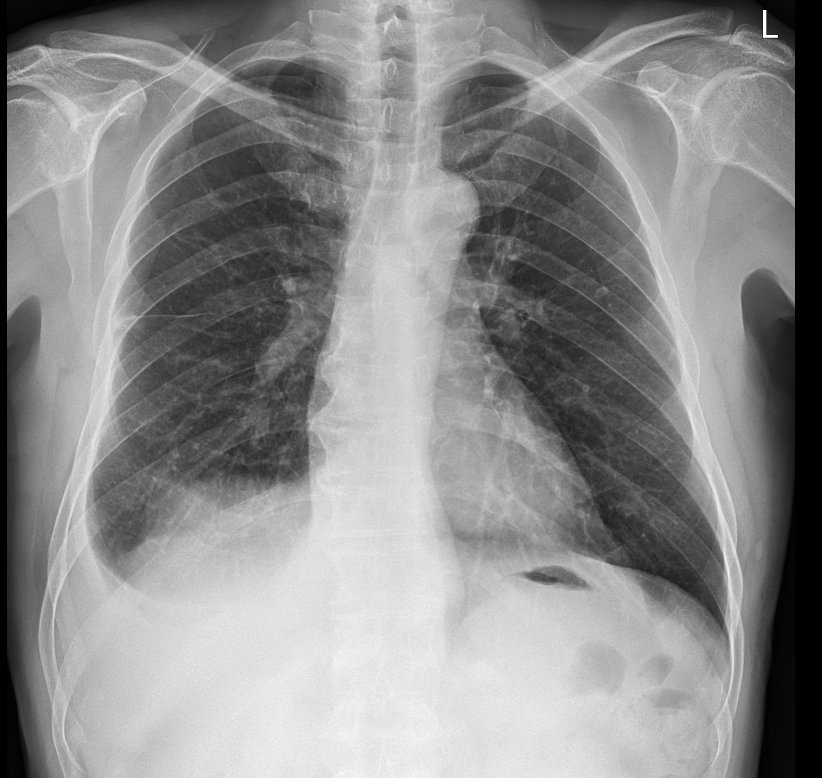

바로 pleural effusion(흉수)가 있거나 의심되는 상황에서 촬영하게 된다. 물병에 물을 담고 병을 세우거나 눕힐 때면 물은 중력에 의해 바닥에 깔리게 된다. 마찬가지로 흉수는 흉강안쪽에 차는 물이기 때문에 서있는 자세에서는 흉강의 가장 아래쪽 갈비뼈와 diaphragm이 만나는 위치인 CPA(costophrenic angle) 쪽으로 물이차게 된다. 따라서 chest PA에서는 해당 부분이 예리하지 않게 blunting 되는 모습을 보인다면 흉수를 의심할 수 있다. 양이 적을 경우엔 애매한 소견이 나타날 수 있는데, 이런 경우 decubitus view를 촬영하게 되면 흉수가 있는지 없는지 알 수 있게 된다.

위 사진을 예시로 보면 Chest PA로는 환자의 우측 흉강에만 흉수가 보인다. decubitus view를 촬영해 보면 우측으로는 흉수가 많이 보이고, 좌측은 적지만 흉수가 있어 보임을 알 수 있다.